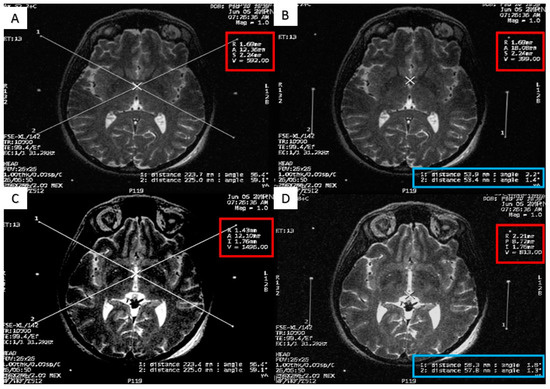

The second method we used to calculate the STN coordinates was direct visualization of the STN on a T2 weighted MRI (Figure 5) [55]. The STN is the almond-shaped hypointense structure located lateral and anterior to the red nucleus. We identified an axial T2 image that showed the largest red nuclei circumference, and then we drew a line from the midline, medial to lateral, along the anterior edge of RN. The center of the STN was chosen at the extension of this straight line about 12 mm from the midline. Then the coordinates were calculated using the same Excel worksheet. Another method of the STN coordinates localization was done in the OR, using the FrameLink software, which is a part of the StealthStation navigation system (Medtronic, Minneapolis, MN, USA) (Figure 6). The software compensates for head and frame tilt in any direction. It allows calculation of the STN coordinates and planning of suitable entry point and trajectory of the DBS electrode that avoid going through the cortical sulci, the ventricles, or any cerebral blood vessels. The final coordinates for the procedure were derived from all the previous techniques and subsequently adjusted using intraoperative electrical microrecording and macrostimulation.

Figure 5. Calculating the subthalamic nucleus (STN) coordinates from the magnetic resonance imaging (MRI) console. (A) Two diagonal lines intersecting at the center of the frame at the STN level with MRI coordinates of the center of the frame shown inside the red square; (B) a crosshair at the center of the left STN, with its MRI coordinates shown inside the red square; two lines are drawn between the middle and lower fiducials on both sides of the frame and their lengths (in the blue rectangle) are used to calculate the Z coordinate; (C) a crosshair at the center of the right STN, with its MRI coordinates shown inside the red square; two line are drawn between the middle and lower fiducials on both sides of the frame and their lengths (in the blue rectangle) are used to calculate the Z coordinate.